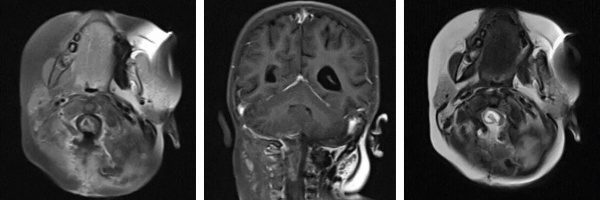

術(shù)后影像(MRI)

然而術(shù)后恢復(fù)之路仍充滿波折。因并發(fā)腦積水,患兒出現(xiàn)嘔吐等癥狀,經(jīng)脫水治療效果不佳。醫(yī)療團隊與家屬充分溝通后,再次為阿什利施行腦室-腹腔分流術(shù),術(shù)后腦積水顯著改善。與此同時,醫(yī)院為她制定并實施了系統(tǒng)化療方案,歷經(jīng)5個周期的藥物調(diào)整與精心治療,至今年7月MRI復(fù)查顯示術(shù)區(qū)強化灶已完全消失。